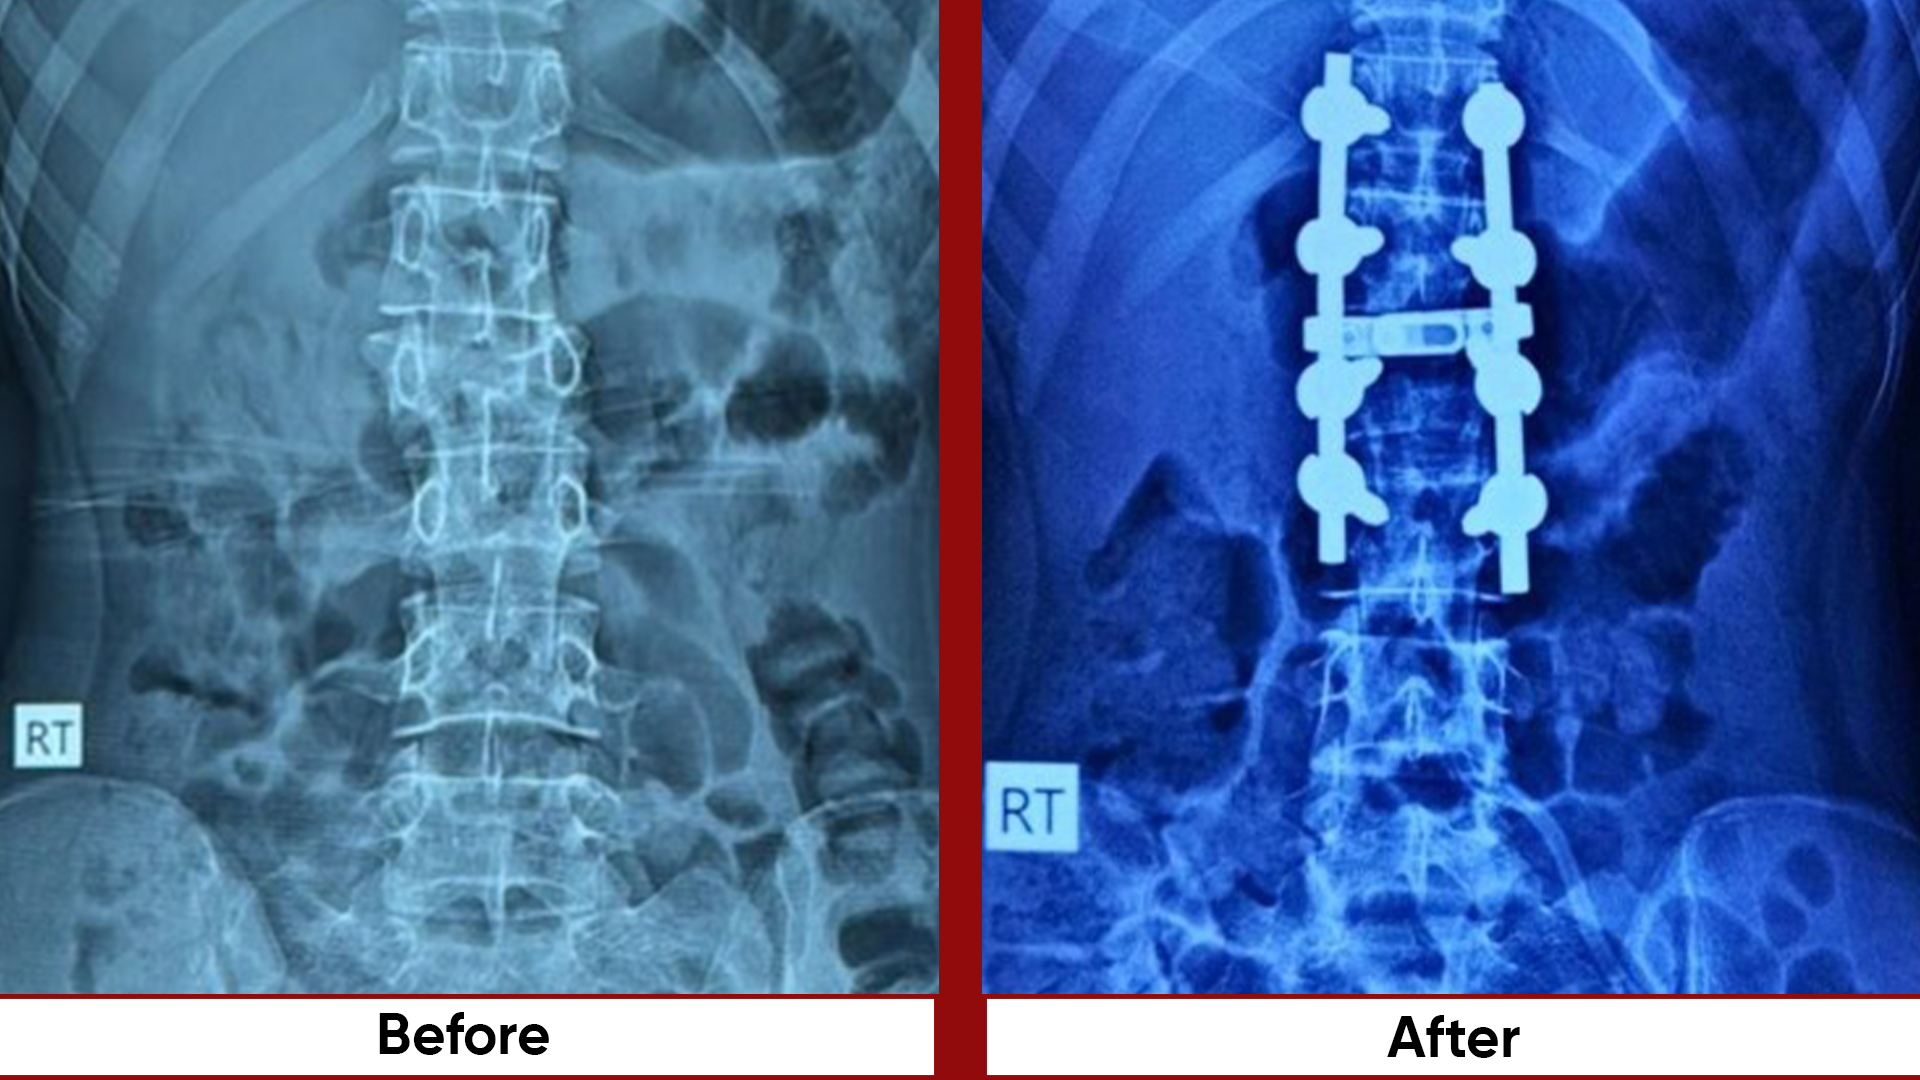

• Fracture Management (simple and complex trauma)

• Pelvic & Acetabular Fracture Fixation